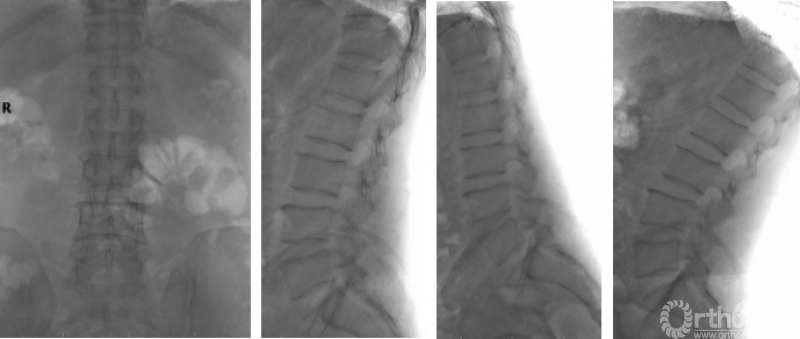

一般情况:患者,男,56岁,主因“间断腰痛30年,加重伴左下肢间歇性跛行2月余”入院。

患者30年前无明显诱因出现下腰部疼痛,2月前无明显诱因出现左臀部、大腿外侧、小腿外侧至足背外侧行走约200米后疼痛,弯腰休息后缓解,MRI提示“腰椎管狭窄症”,入院行2周保守对症治疗后疼痛缓解出院。1个月后,患者再次就诊于门诊,此次行走约50m即出现左下肢放射痛,位置同前。

查体:视触动量等检查均无明显阳性体征,病理征、四肢腱反射等神经查体均正常。核磁提示:L3/4、L4/5椎管狭窄,L3/4纤维环HIZ,L4/5左侧隐窝狭窄,L5/S1纤维环HIZ。腰椎稳定性可。(图7)

入院诊断:腰椎管狭窄症(L3/4、L4/5);高血压2级。

图7

图8

困惑:L3-5节段椎管狭窄,纤维环存在HIZ,腰痛来源不明。患者症状为狭窄,查体未诱发出明显阳性体征,无法精确定位责任节段。为保证手术效果,开放手术需解除L3-5两个节段狭窄,创伤相对较大。患者对开放手术抵触,要求微创治疗。